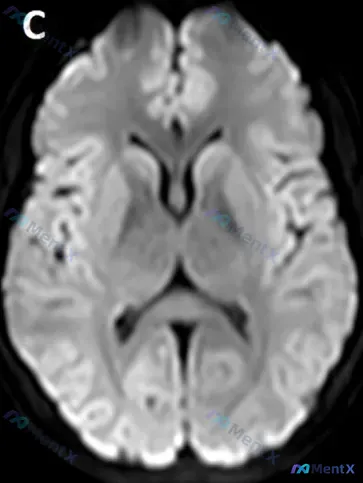

整理到一份脑部MRI的读片分析,核心特征很突出: - 序列:发病第3天的脑部MRI-DWI - 影像表现:双侧大脑皮层(尤其是顶枕叶交界区、枕叶)出现显著的对称性高信号,沿皮层回分布,像“缎带征” - 关键排除点:形态不是楔形/扇形,不符合单一血管(MCA/PCA)供血区的典型分布 这份资料里没有附...